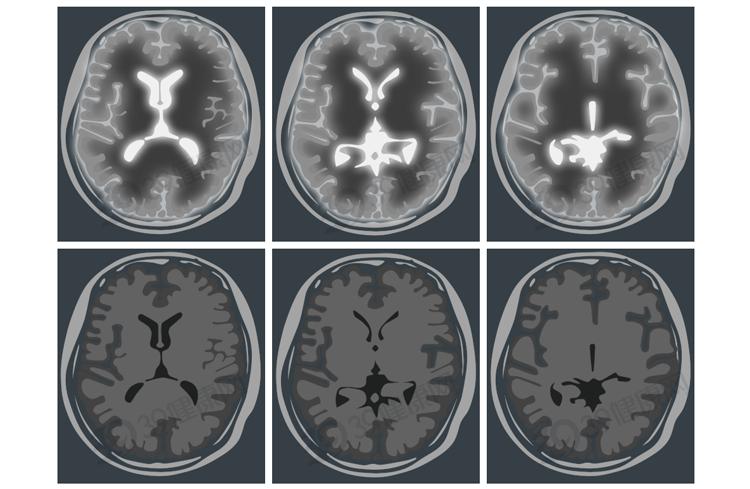

CT(计算机断层扫描)是一种高精度医学影像检查,能够通过X射线获取身体内部的详细图像,帮助医生快速、准确地判断疾病。

其主要有两种类型:平扫CT、增强CT。区别在于是否使用造影剂、成像效果以及适用场景。

平扫CT是最基础的类型,属于无创检查,不使用造影剂,直接进行X射线扫描,适用于基础检查,如脑出血、肺炎、骨折等。

增强CT则需要在检查前通过静脉注射造影剂,让血管、器官、病变部位更为清晰,多用于判断肿瘤良恶性、血管病变、脏器功能异常等。

比如脑梗死、脑出血、颅内占位、头皮下血肿等头部问题;

核磁共振(MRI)的原理则有点像把水分子“摇一摇”。

它用强大的磁场和无线电波,让体内的水分子先激动起来,再慢慢恢复平静。恢复过程中释放的信号,就能形成详细的图像,就像“听”水分子的回声。

辐射量为0(没有电离辐射!),适用于脑部、关节、软组织病变等精细检查。